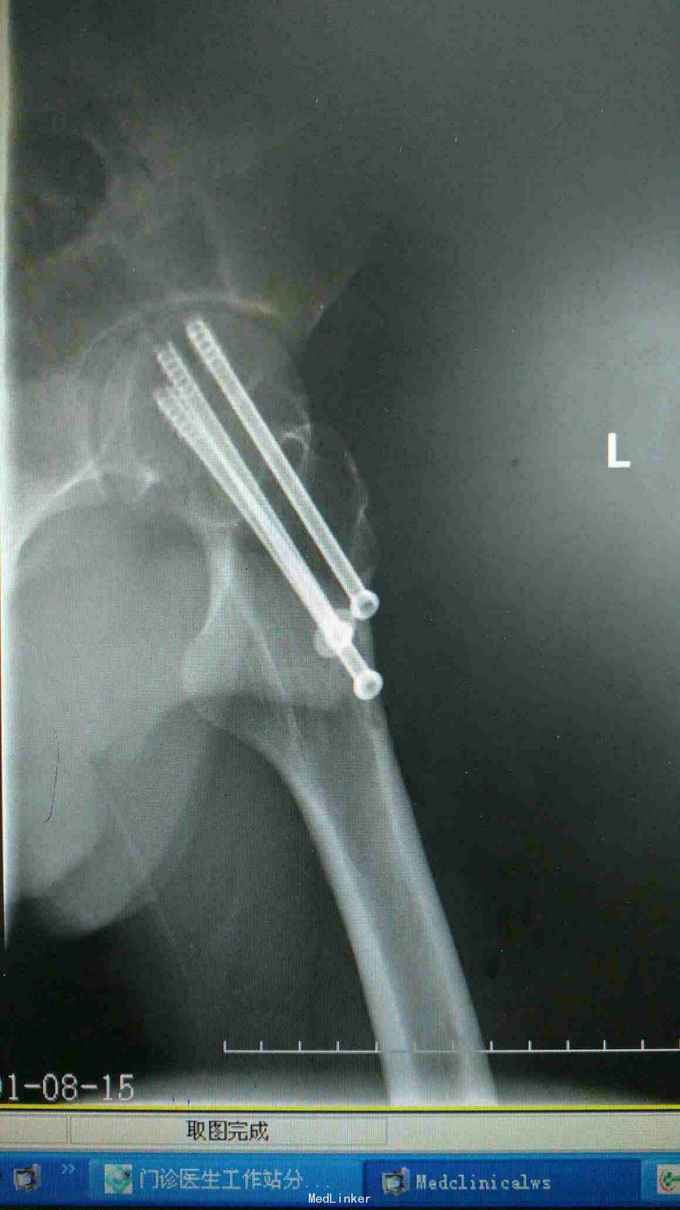

24岁男性,运动中摔倒致左髋疼痛活动受限,

左髋部压痛,大粗隆扣痛,下肢杆力消失,x光及CT证实左股骨颈骨折

左股骨颈骨折 急诊手术,闭合复位空心钉内固定术